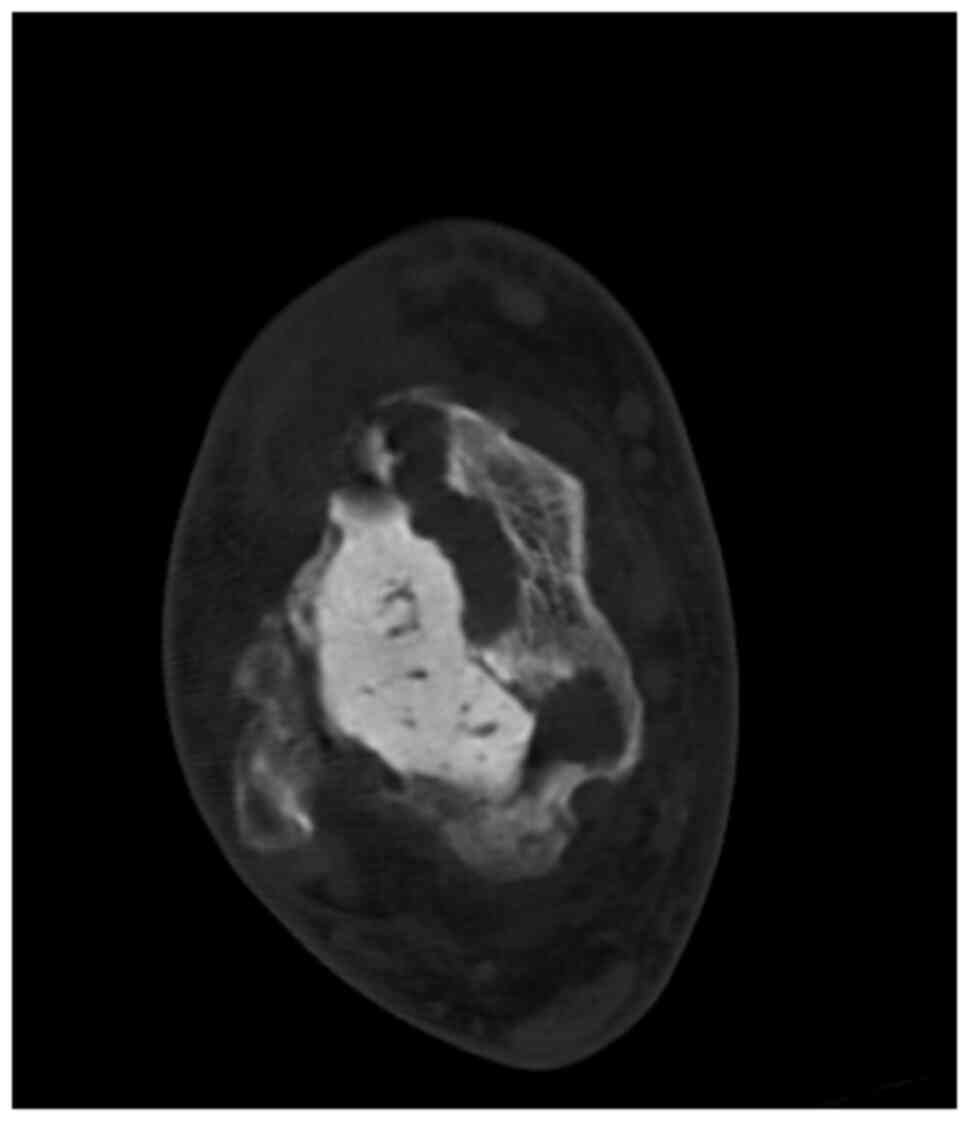

In June 2007, a 50-year-old male presented to the Masaryk Memorial Cancer Institute Sarcoma Center, with a 1-month history of persistent pain in the right ankle. Further investigations showed a cystic lesion of the talus on a CR scan, which was later confirmed by a supplementary CT scan (Fig. 16). The histopathology report diagnosed GCTB with a secondary aneurysmal cyst of the talus (Fig. 17), leading to a recommendation for intralesional resection with bone cement augmentation. After receiving the recommended treatment, the patient returned 5 months later with swelling and increased pain in the ankle. A follow-up CT scan showed destruction of the bone surrounding the bone cement, as well as osteolysis of the calcaneus and the presence of an extraosseous mass proximally (Figs. 16 and 18). Due to the extent of osteolysis, the patient required an astragalectomy. Subsequent histopathology reports showed a diagnosis of giant-cell rich osteosarcoma, contradicting the initial findings (Fig. 19). Further staging scans indicated the presence of lung metastases (Fig. 20). The Musculoskeletal Tumor Committee recommended metastasectomy followed by adjuvant CHT. Despite the successful removal of 12 lung metastases, the patient developed additional lung metastases within two months. Despite palliative care efforts, the patient died 6 months later.

Figure 16.

Case 4. (A) Radiographic images showing a misdiagnosed cystic lesion of the talus (right) alongside the post-cementoplasty results (left). (B) CT scan images showing local recurrence following cementoplasty, initially performed for a misdiagnosed giant-cell rich osteosarcoma

Figure 19.